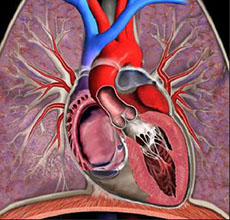

冠状动脉粥样硬化性心脏病

疾病介绍:冠状动脉粥样硬化性心脏病是冠状动脉血管发生动脉粥样硬化病变而引起血管腔狭窄或阻塞,造成心肌缺血、缺氧或坏死而导致的心脏病,常常被称为“冠心病…【详细】